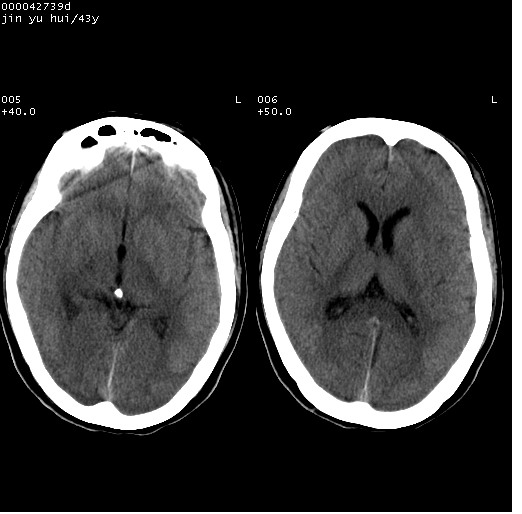

患者 女,43岁。头部外伤26天,经住院治疗,现头痛减轻。申请ct复查,了解颅内情况。

临床诊断:2级脑外伤。

颅脑ct轴位平扫(层厚、层距均为10mm),图像如下:

伴硬膜下水瘤

纵裂旁硬膜下水瘤,左额部头皮肿胀

大脑镰左旁硬膜下血肿慢性期。

大脑镰左旁慢性硬膜下血肿.

大脑镰左旁慢性硬膜下血肿.左额部头皮血肿.

是不是应该为:大脑镰左旁硬膜下血肿吸收期更妥当些;